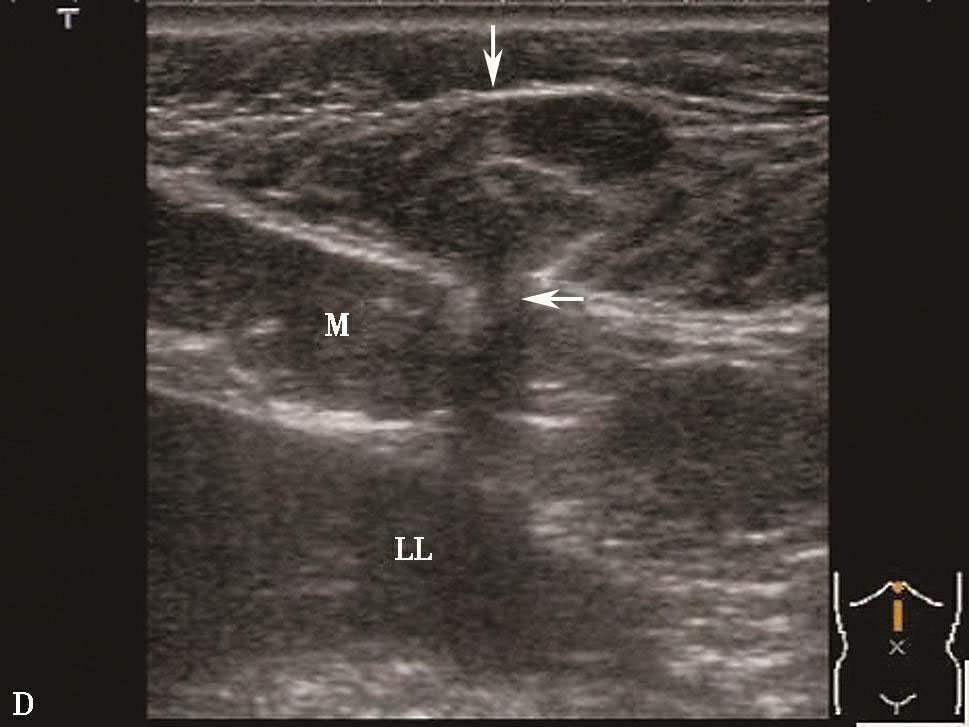

腹壁疝超声图片

腹壁疝彩超报告图片

腹壁疝超声报告模板